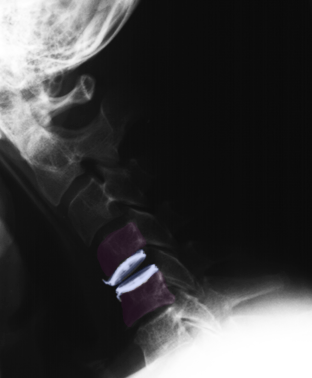

Πρόσθια αυχενική δισκεκτομή και τοποθέτηση τεχνητού αυχενικού δίσκου (μπλέ) Α6-Α7. |

Πρόσθια αυχενική δισκεκτομή και τοποθέτηση τεχνητού αυχενικού δίσκου (μπλέ) Α6-Α7. Ακτινογραφίες με τον αυχένα σε ουδέτερη θέση (αριστερά), έκταση (κέντρο) και κάμψη (δεξιά). Αναδεικνύεται η κίνηση στο χειρουργημένο μεσοσπονδύλιο διάστημα. |